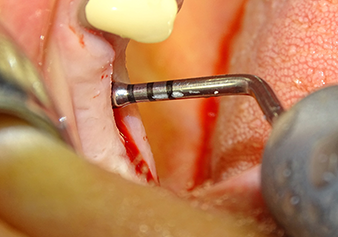

Затем, с помощью инструмента I2A (диаметр 2,0 мм), дно пазухи перфорировалось периодически и в минимально возможном диапазоне. Этот специфический пьезохирургический метод гарантирует, что мембрана Шнейдера не будет повреждена. При использовании Z25P, мембрана уже была слегка приподнята охлаждающей жидкостью, подаваемой через наконечник инструмента (рис. 3). Во избежание высокого давления в ложе имплантата, количество охлаждающей жидкости составляло не более 50%.

The Schneiderian membrane is carefully detached with the Z25P instrument (phase 1)

Рис.3: После маркировки положения имплантата и первоначального расширения ложа, мембрана Шнейдера деликатно отделяется с помощью инструмента Z25P (фаза 1).